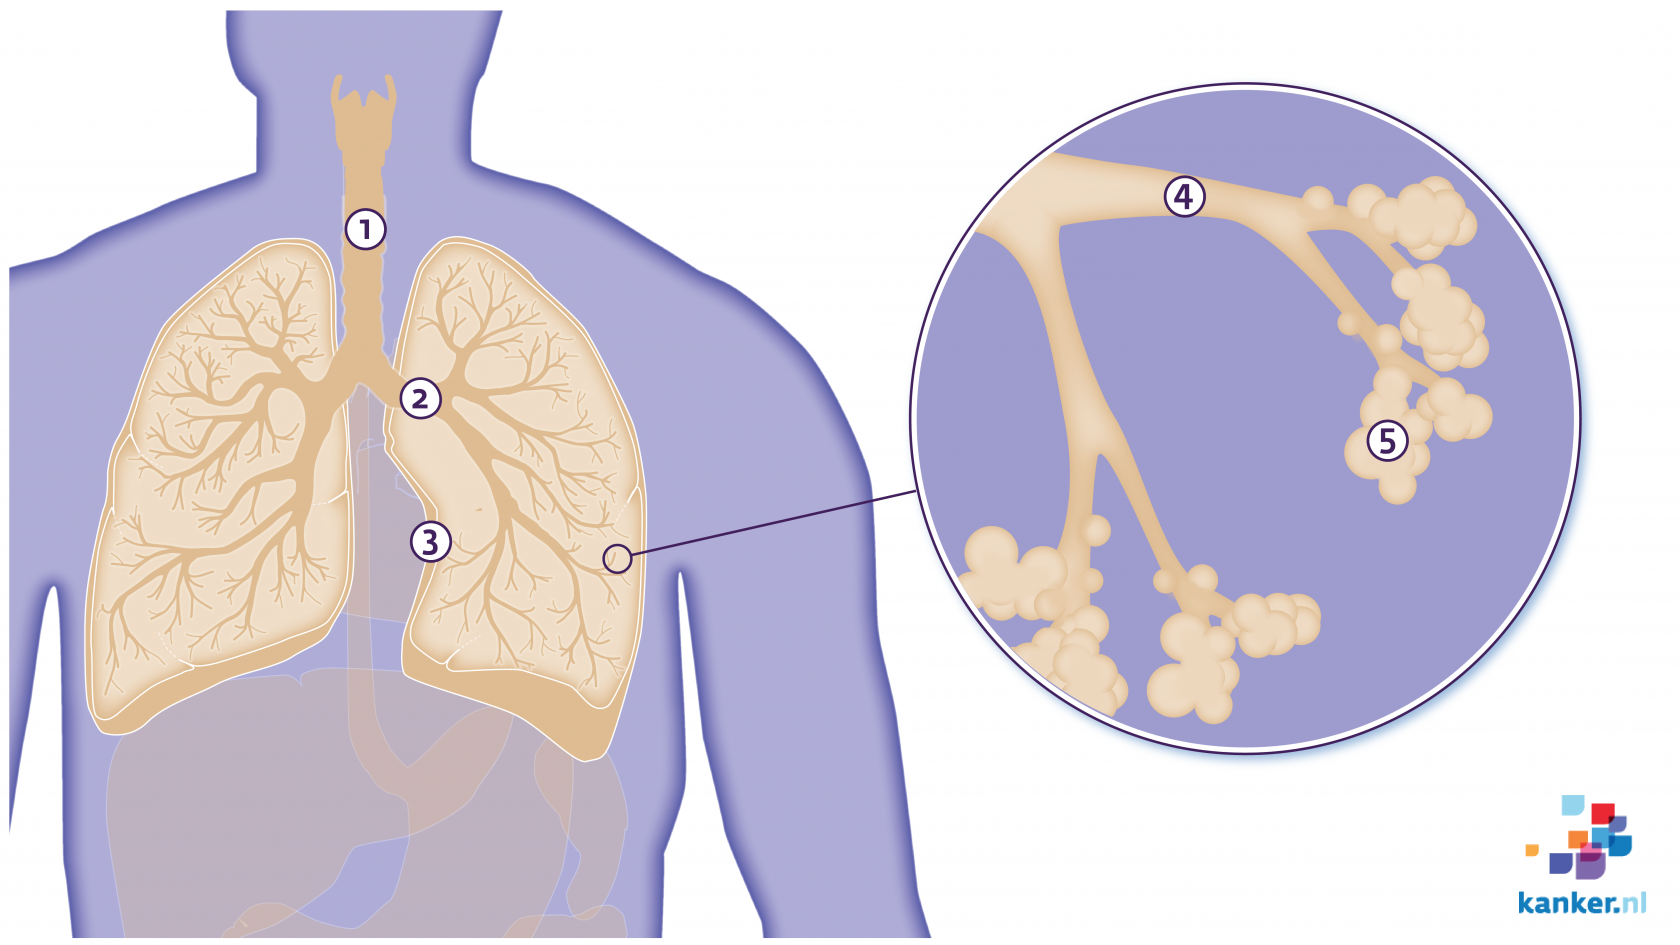

De longen Kanker.nl

Longen En Luchtwegen

Longen Mijn Gezondheidsgids

Longen